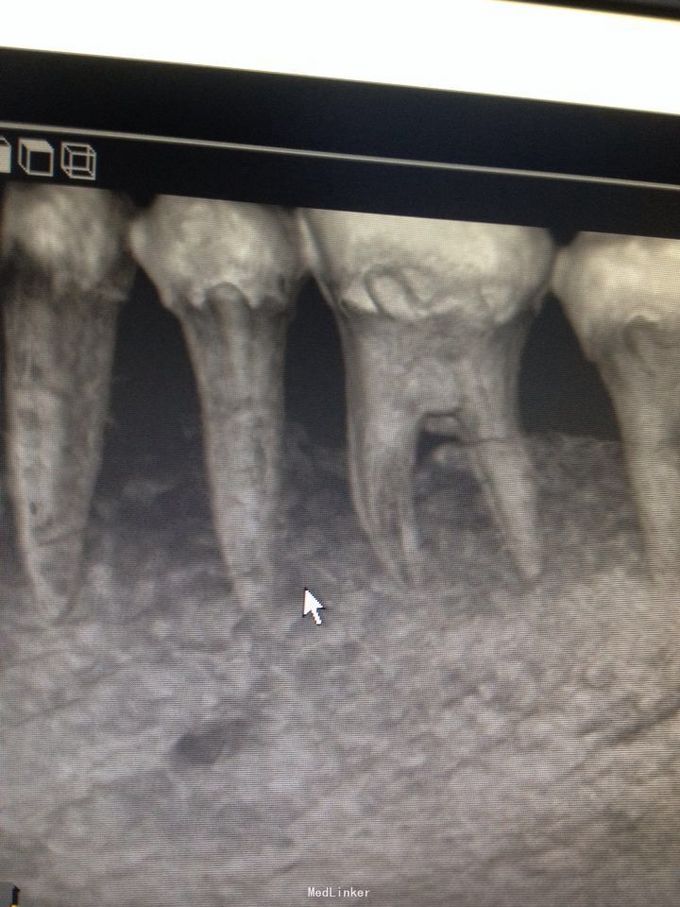

牙根纵折

询问病史有咬硬物硌牙史。诊断:牙根纵折,慢性根尖周炎急性发作。 局麻下微创拔除。

请教是否可以采用分牙方法,保留未折裂牙根,与后临牙联冠或复合桥方法修复?后期效果如何?